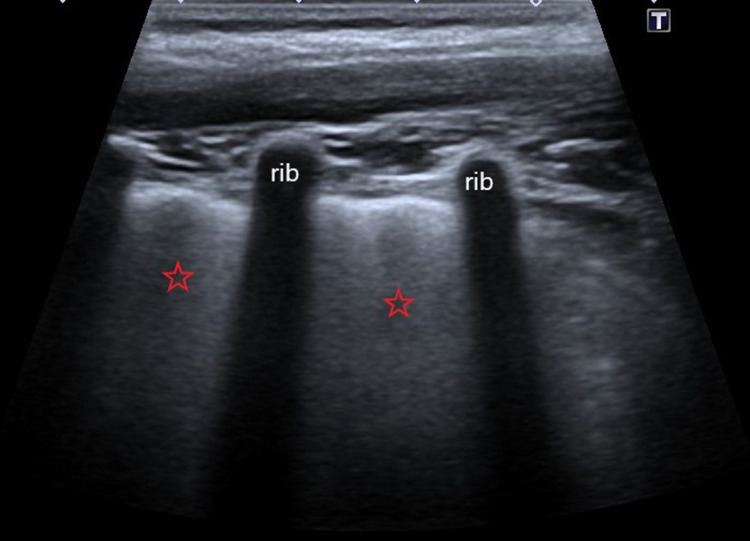

Picture 4.

Ultrasound profile 1, confluent B-lines or “white lungs” (red stars)

Distance between B lines points to alveolar or interstitial presentation, so we can differentiate between “white lung”—alveolar presentation or confluent B lines-interstitial presentation [9].